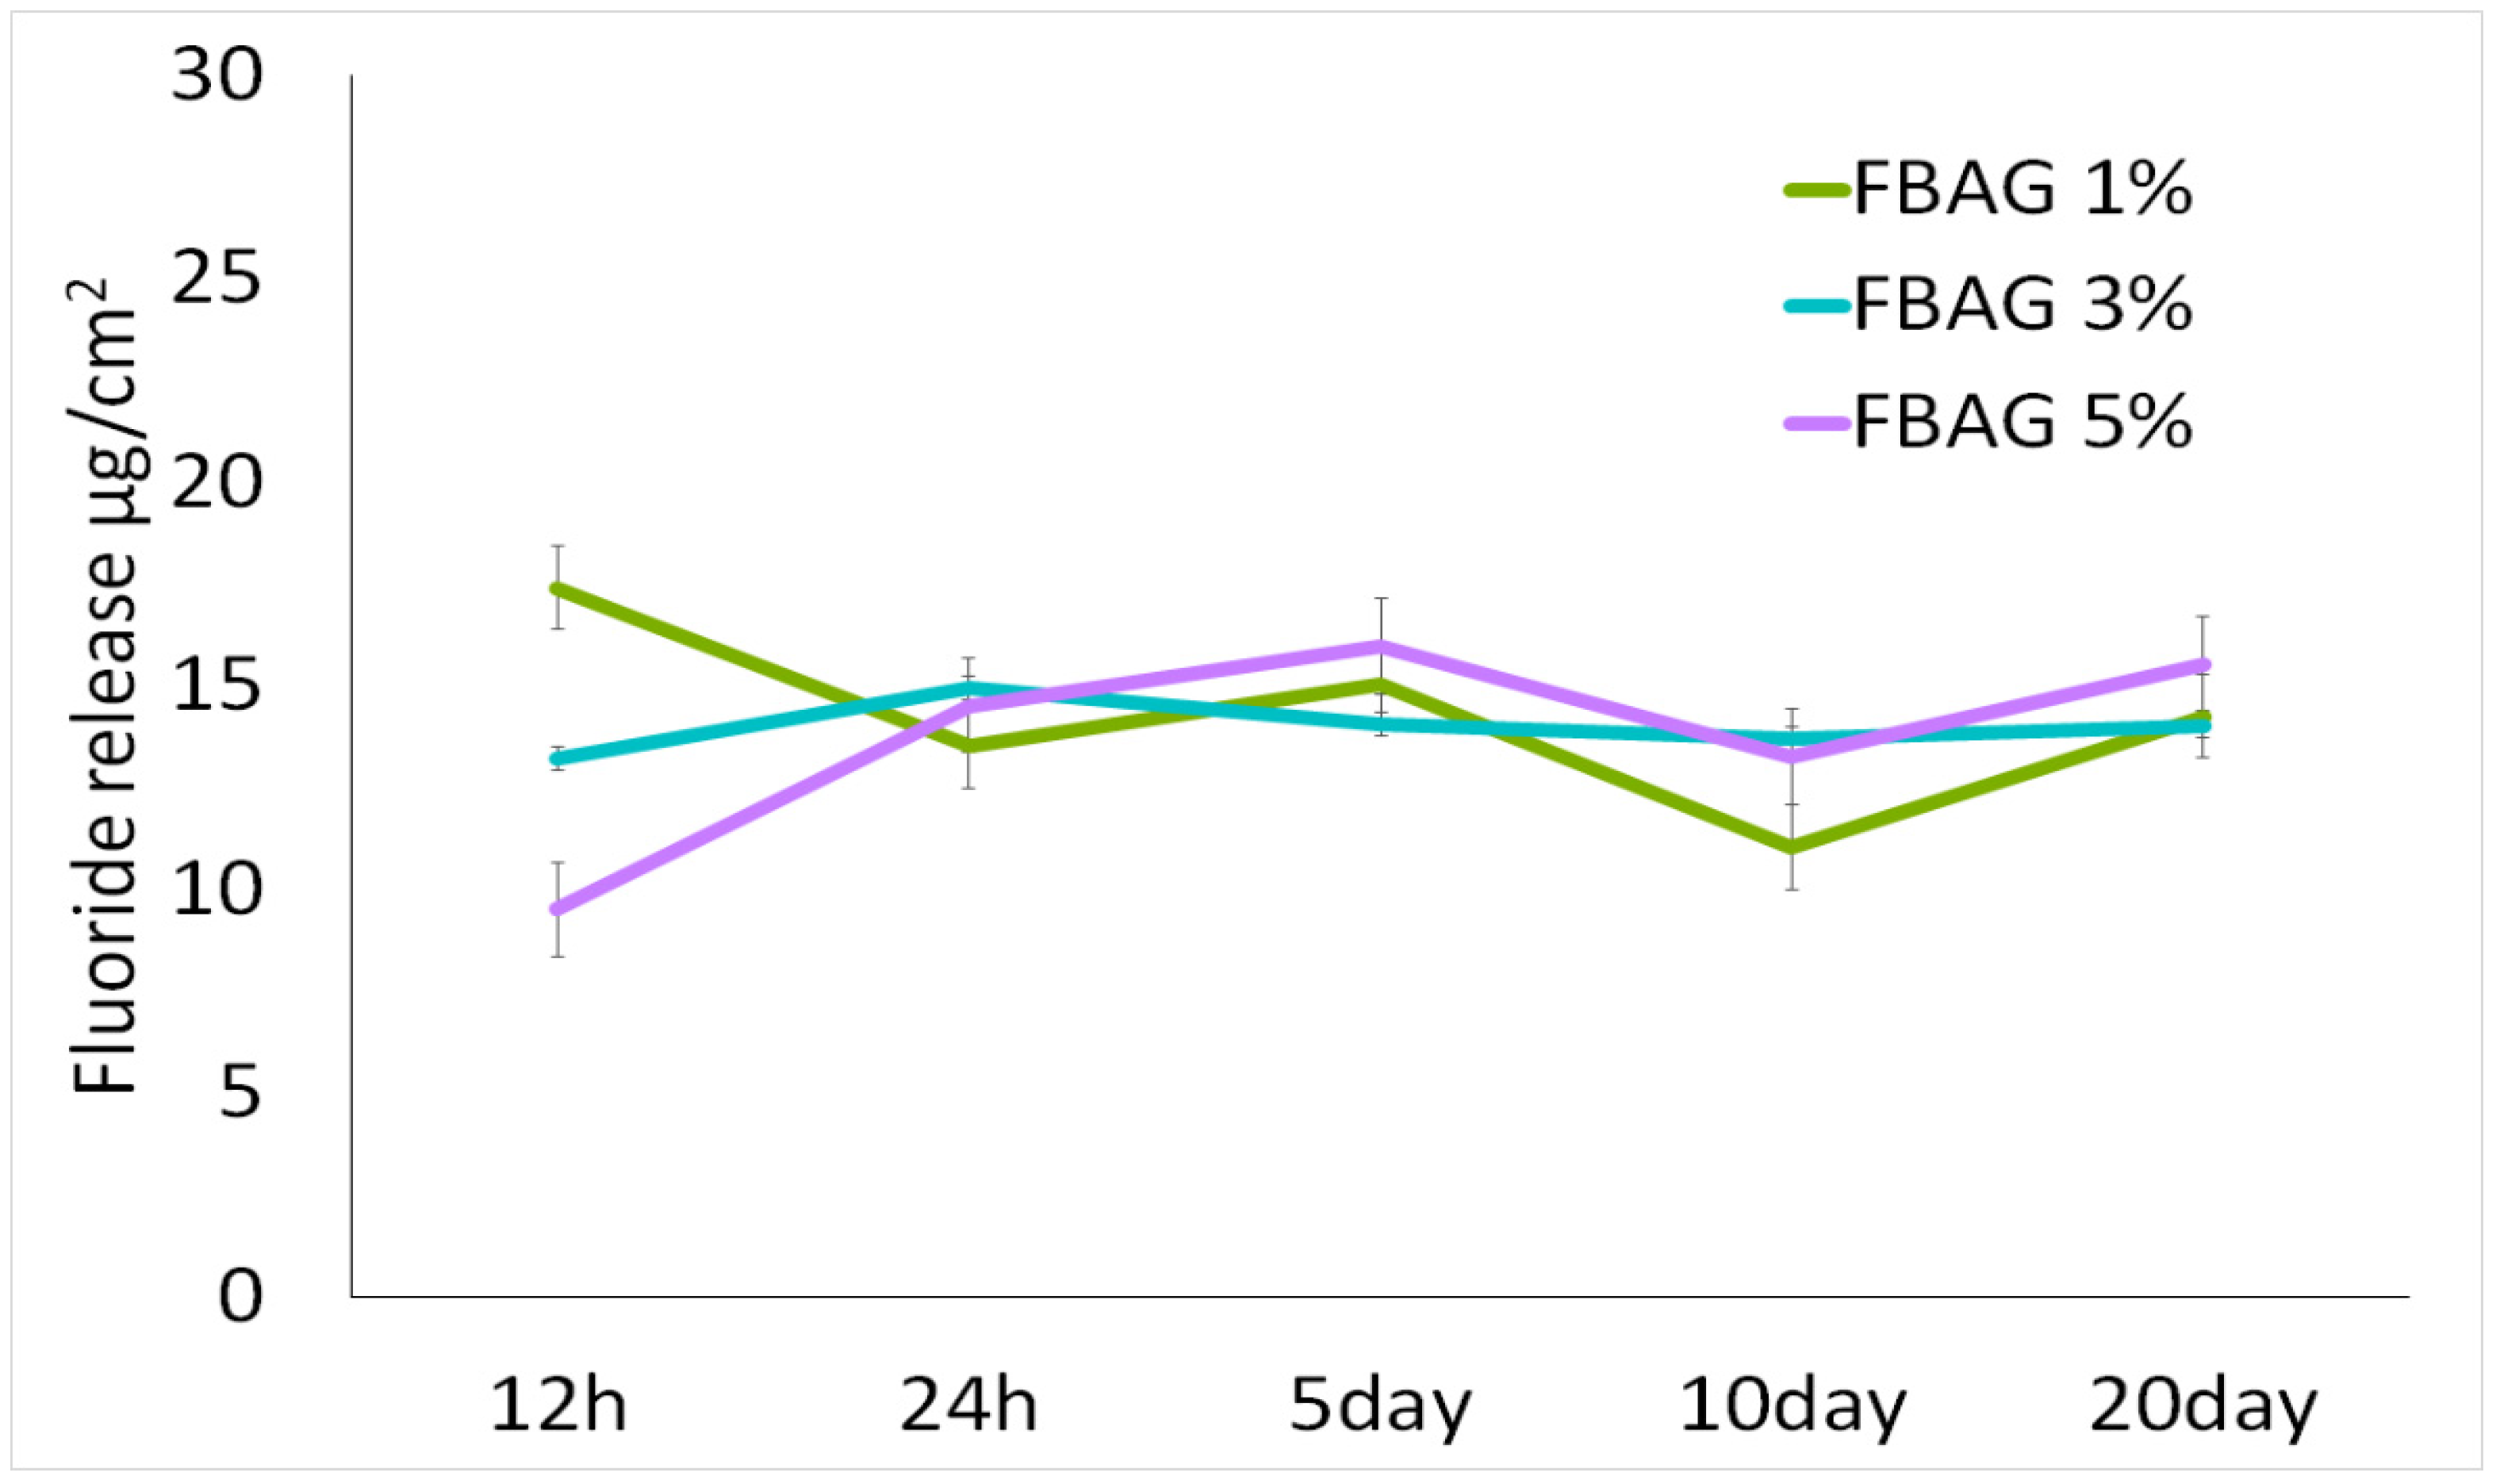

3.7. In Vitro F Dissolution Test